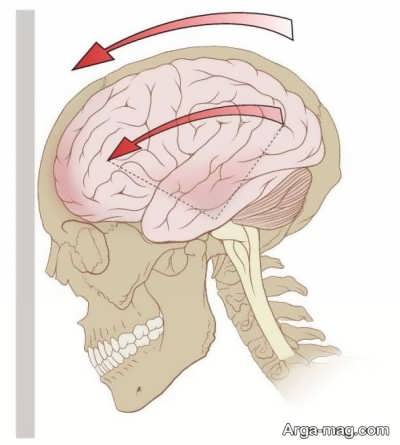

زنان دو برابر مردان سردرد بالای سر و پیشانی را تجربه می کنند. بسیاری از افرادی که این سردرد را تجربه می کنند به طور معمول شصت تا نود روز با آن درگیر هستند. جالب است که هیچ دلیل خاصی برای این سردردها وجود ندارد و اغلب به خاطر فشار کاری، استرس و گاهی به علت انقباض عضلات پشت گردن و پوست سر دچار آن می شوند.

دلیل ایجاد سردرد بالای سر می تواند نداشتن استراحت و خواب کافی، وجود استرس های ذهنی و احساسی از جمله افسردگی، اضطراب، خستگی، گرسنگی و پایین بودن سطح آهن خون باشد.

درد و فشار ملایم در پیشانی، طرفین و بالای سر، آغاز سردرد از میانه های روز، مشکلات خوابیدن، احساس خستگی، حساسیت، مشکل در تمرکز، درد عضلات و حساسیت به نور و صدا از جمله نشانه های اینگونه سردرد ها هستند.